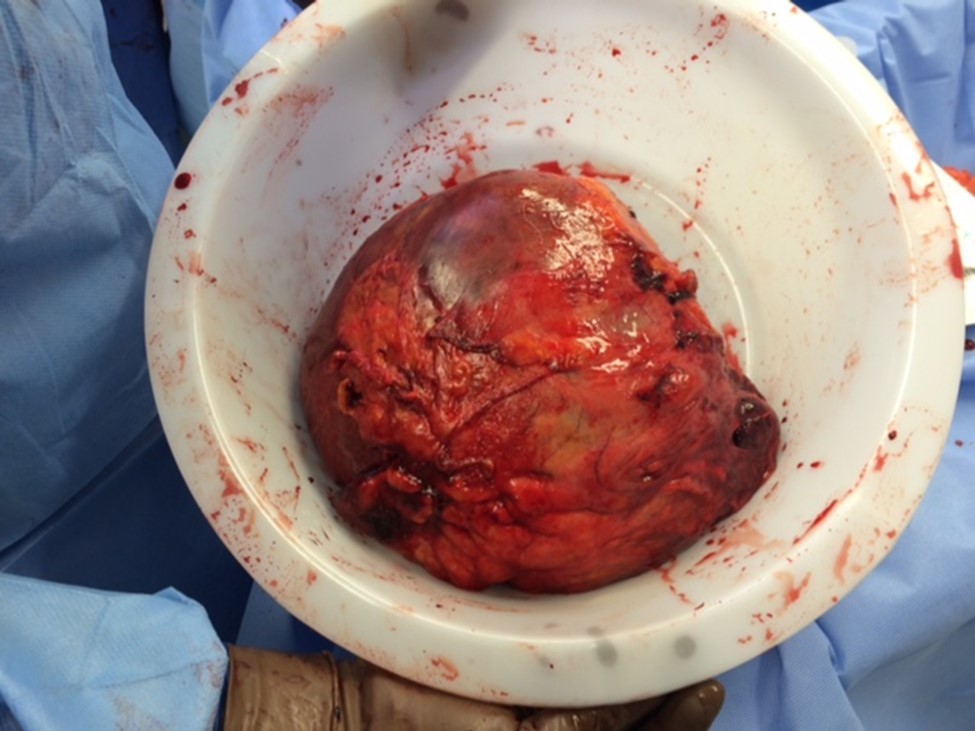

A plain abdominopelvic CT showed massive splenomegaly with high attenuation areas suspicious for hematoma, as well as free fluid in the abdomen (Figure 1). The patient was immediately started on a transfusion of packed red blood cells and taken emergently to the operating room. A laparotomy was performed and the patient was found to have a massive, ruptured spleen with 1500 mls of frank blood in the peritoneal cavity. Splenectomy and abdominal washout were done. The spleen measured 21 x 19 x 10 cm and weighed 2870 grams. It is shown below (Figure 2).

Figure 2.Spleen following removal – medial and hilar aspect shown. Arrow points to area of rupture.

1. Postoperatively, the patient recovered well and was discharged 4 days later. Pathology of the spleen showed a predominance of maturing myeloid cells and was consistent with chronic myelomoncytic leukemia (CML).